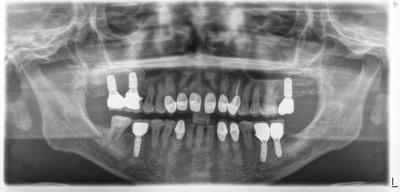

HOME > ブログ 一覧 > インプラント包括ケース 2021.04.17インプラント包括ケース 本ケースは以前にご紹介したかも? 使用インプラントはアストラ(スウェーデン)。 上顎左右インプラント部に行ったサイナスリフトも安定していて周囲骨と同化=自身の骨に置換している メインテナンス中。 Recent Entries アライナー矯正(インビザライン、シュアスマイル)費用を2023年 1月から改訂させていただきます(01/09) 本年もよろしくお願いいたします(01/02) 年始の診療について(01/01) 新しいWEBへ移行、年末年始の診療のお知らせ(12/29) ダラダラ根管治療行っても治らないという事(12/21) Category その他の治療(126) インビザライン・矯正(52) インプラント治療(216) ホワイトニング(47) メインテナンス(21) 包括診療(95) 医院からのお知らせ(249) 審美治療(128) 日々雑感(283) 根管治療(100) 歯周病治療(90) 矯正(73) 補綴治療(45) 補綴治療カテゴリを追加(1) 診療全般(44) Archive 2023年1月(3) 2022年12月(6) 2022年11月(14) 2022年10月(6) 2022年9月(8) 2022年8月(7) 2022年7月(13) 2022年6月(8) 2022年5月(7) 2022年4月(7) 2022年3月(6) 2022年2月(7)